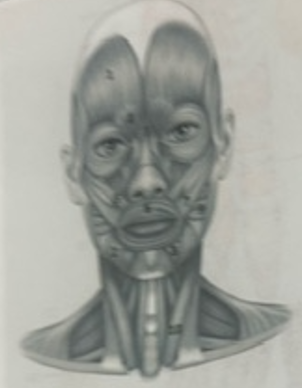

What muscle is 1?

Frontalis

What muscle is 2?

Depressor anguli oris

What muscle is 3?

Depressor labili inferioris

What muscle is 4?

Corrugator supercili

What muscle is 5?

Orbicularis oris

What muscle is 6?

Zygomaticus minor

What muscle is 7?

Zygomaticus major

What muscle is 9?

Buccinator

What muscle is 10?

Sternocleidmastoid

What muscle is 11?

Temporalis

What muscle is 12?

Masseter

What muscle is 13?

Risorius